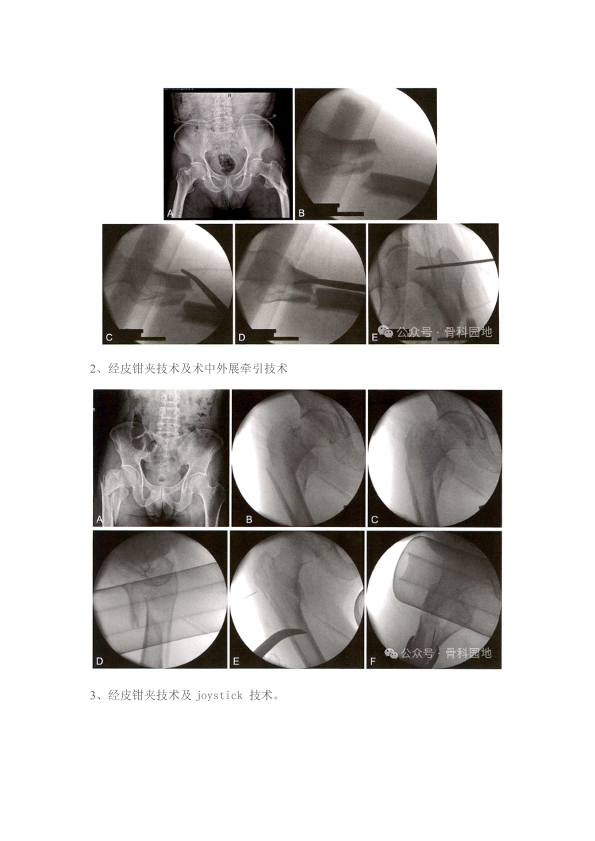

转子下骨折复位难?髓内钉精准复位技巧